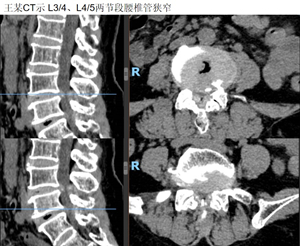

首先是王某,双下肢麻木2年余、加重1月。入院行L3/4、L4/5两节段肌间隙入路下腰椎融合手术。术后3天拔管,5天出院。

术后引流量仅25ml